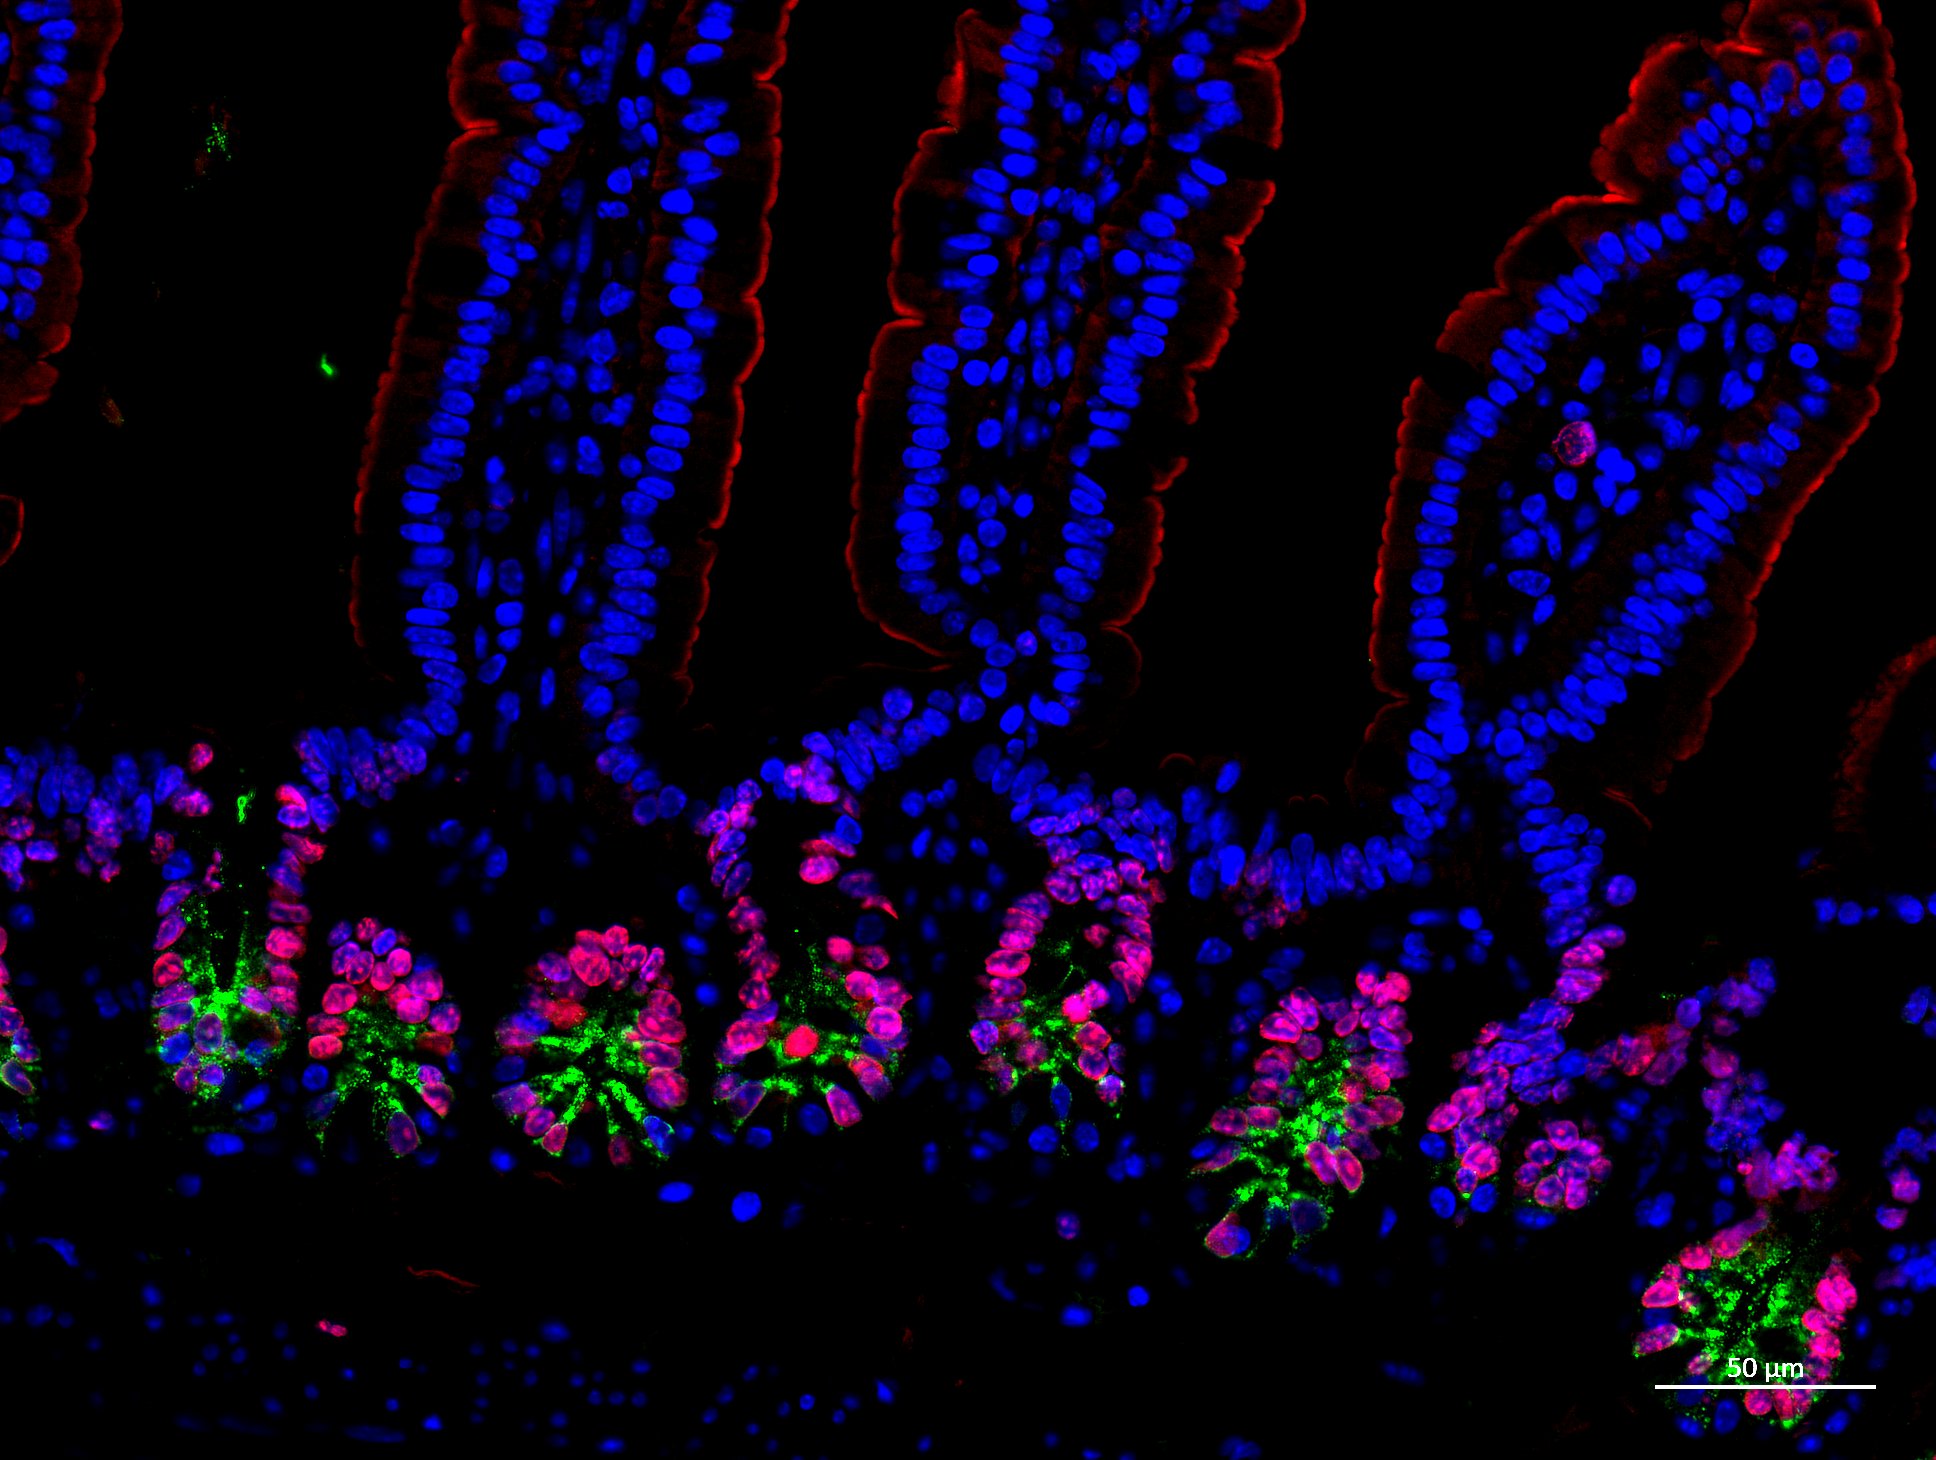

| 2. | Research | /research/ |

| 7. | Inflammation | /research/inflammation/ |

| 9. | Microbiome | /research/microbiome/ |

| 10. | Crohns disease and fistula | /research/inflammation/crohn-s-disease-and-fistula/ |